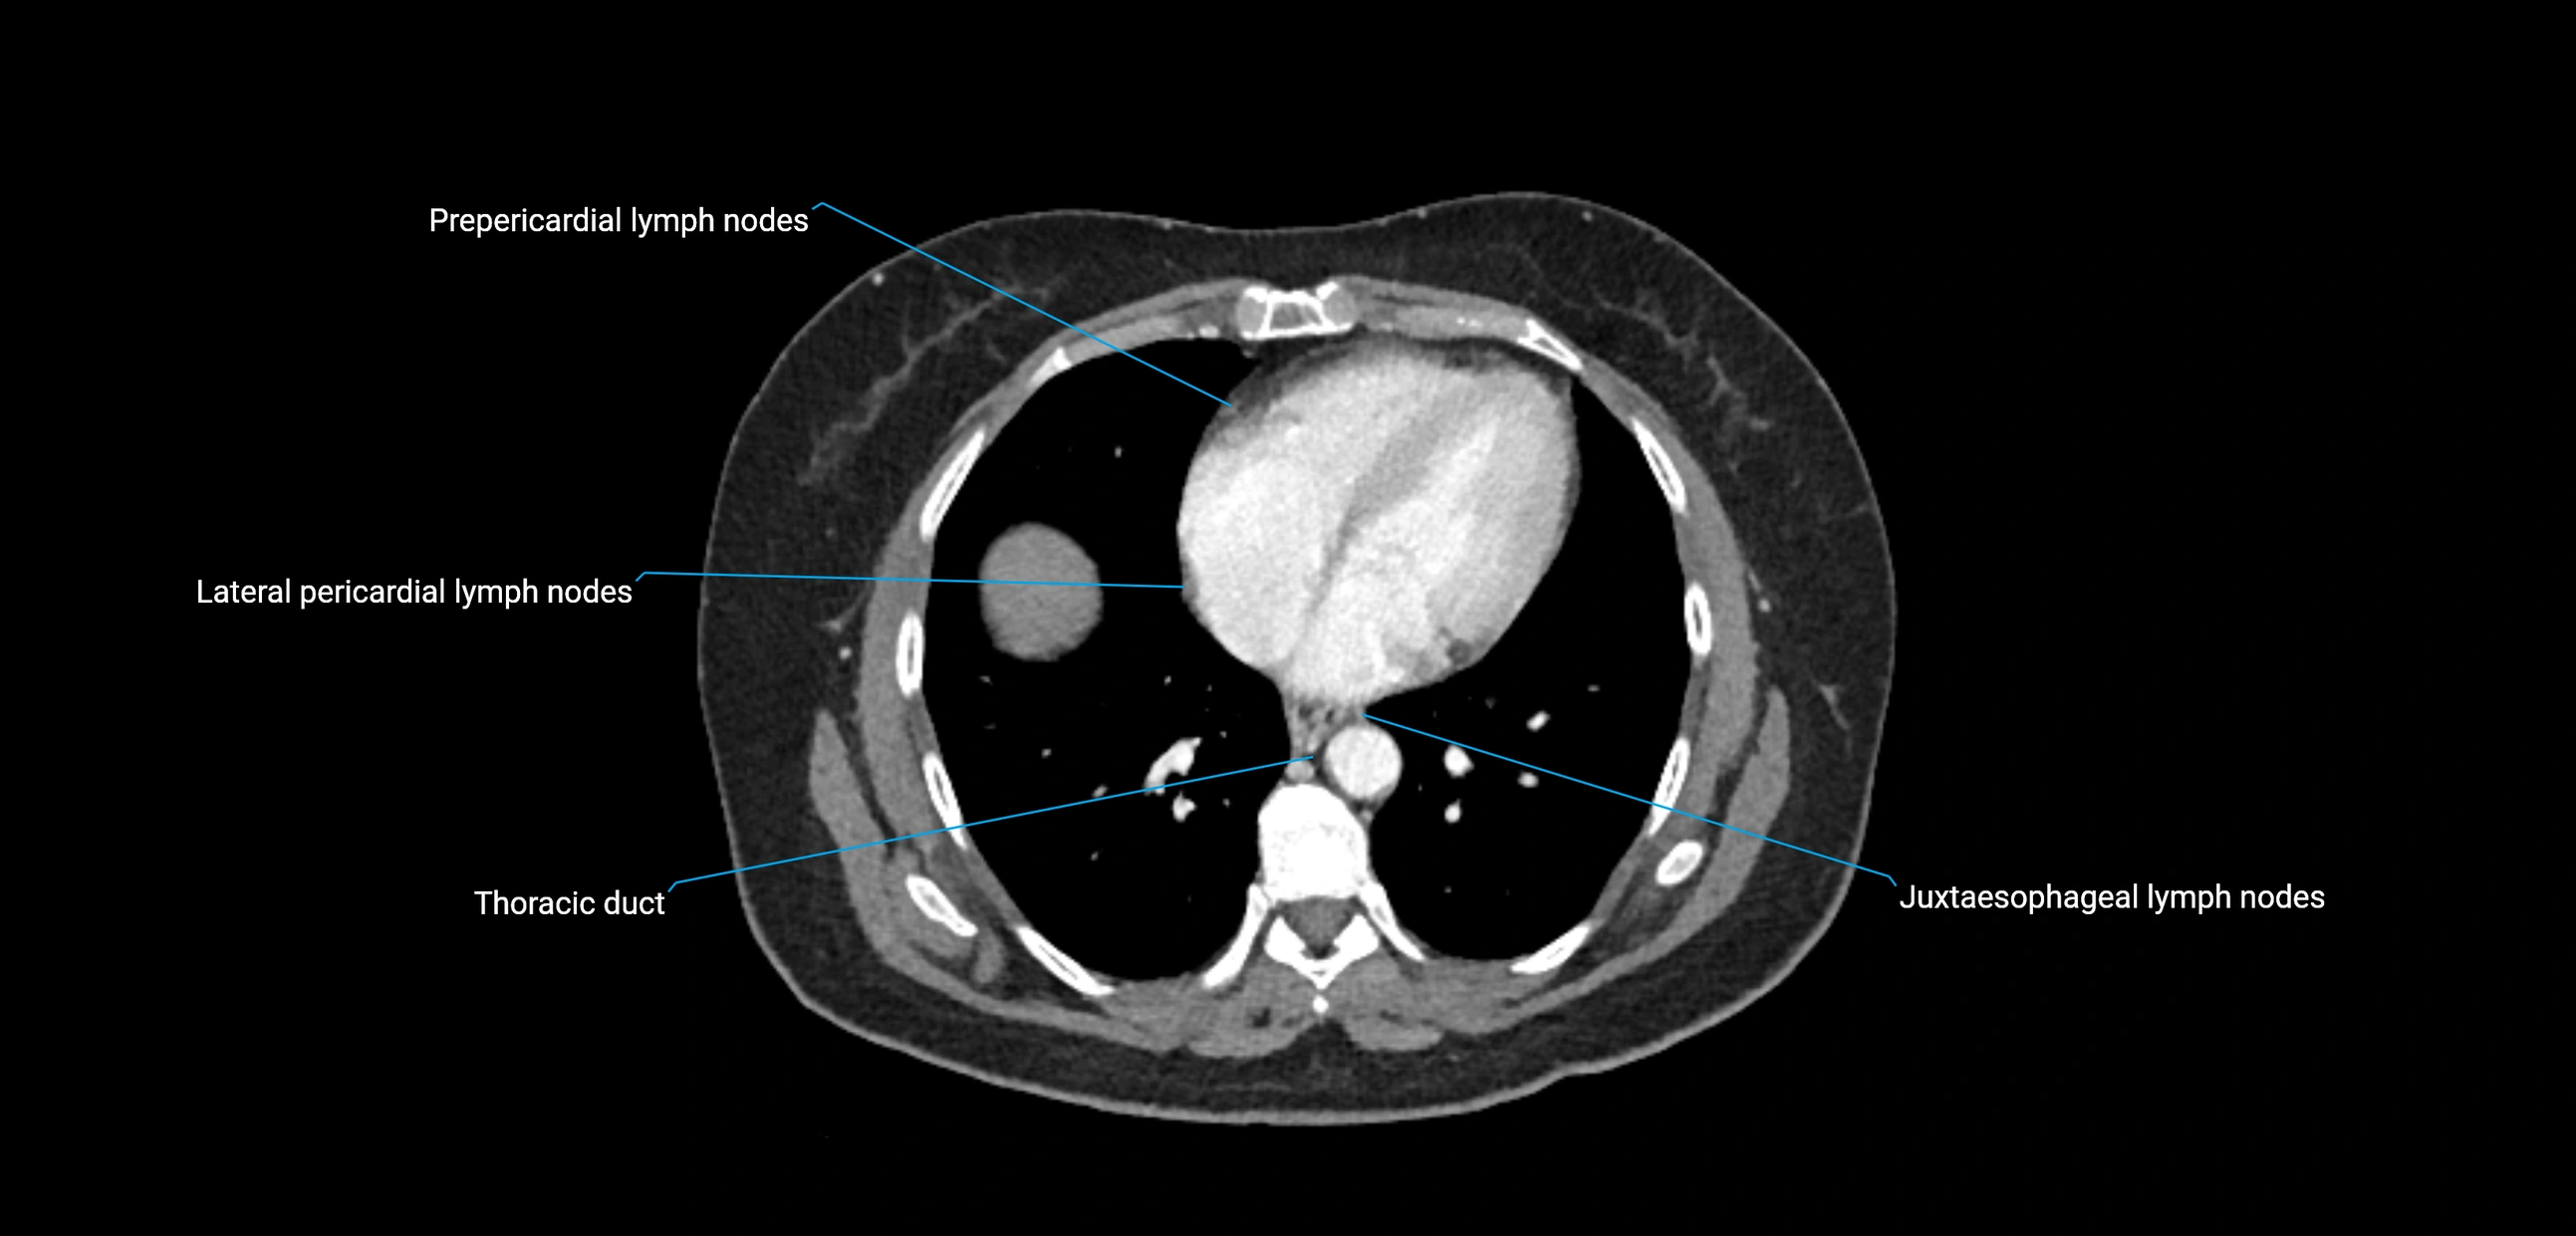

CT image

image